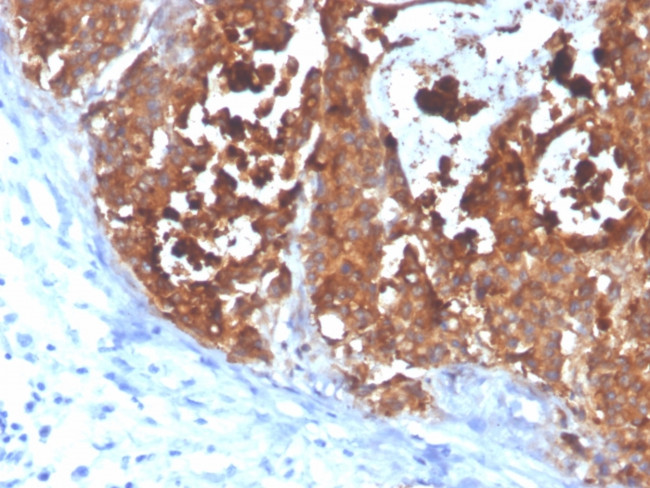

Carcinoembryonic Antigen (CEA)/CD66e Antibody in Immunohistochemistry (Paraffin) (IHC (P))

Formalin-fixed, paraffin-embedded human colon carcinoma stained with CEA Mouse Monoclonal Antibody (C66/4098). {{ $ctrl.currentElement.advancedVerification.fullName }} 验证信息 View more